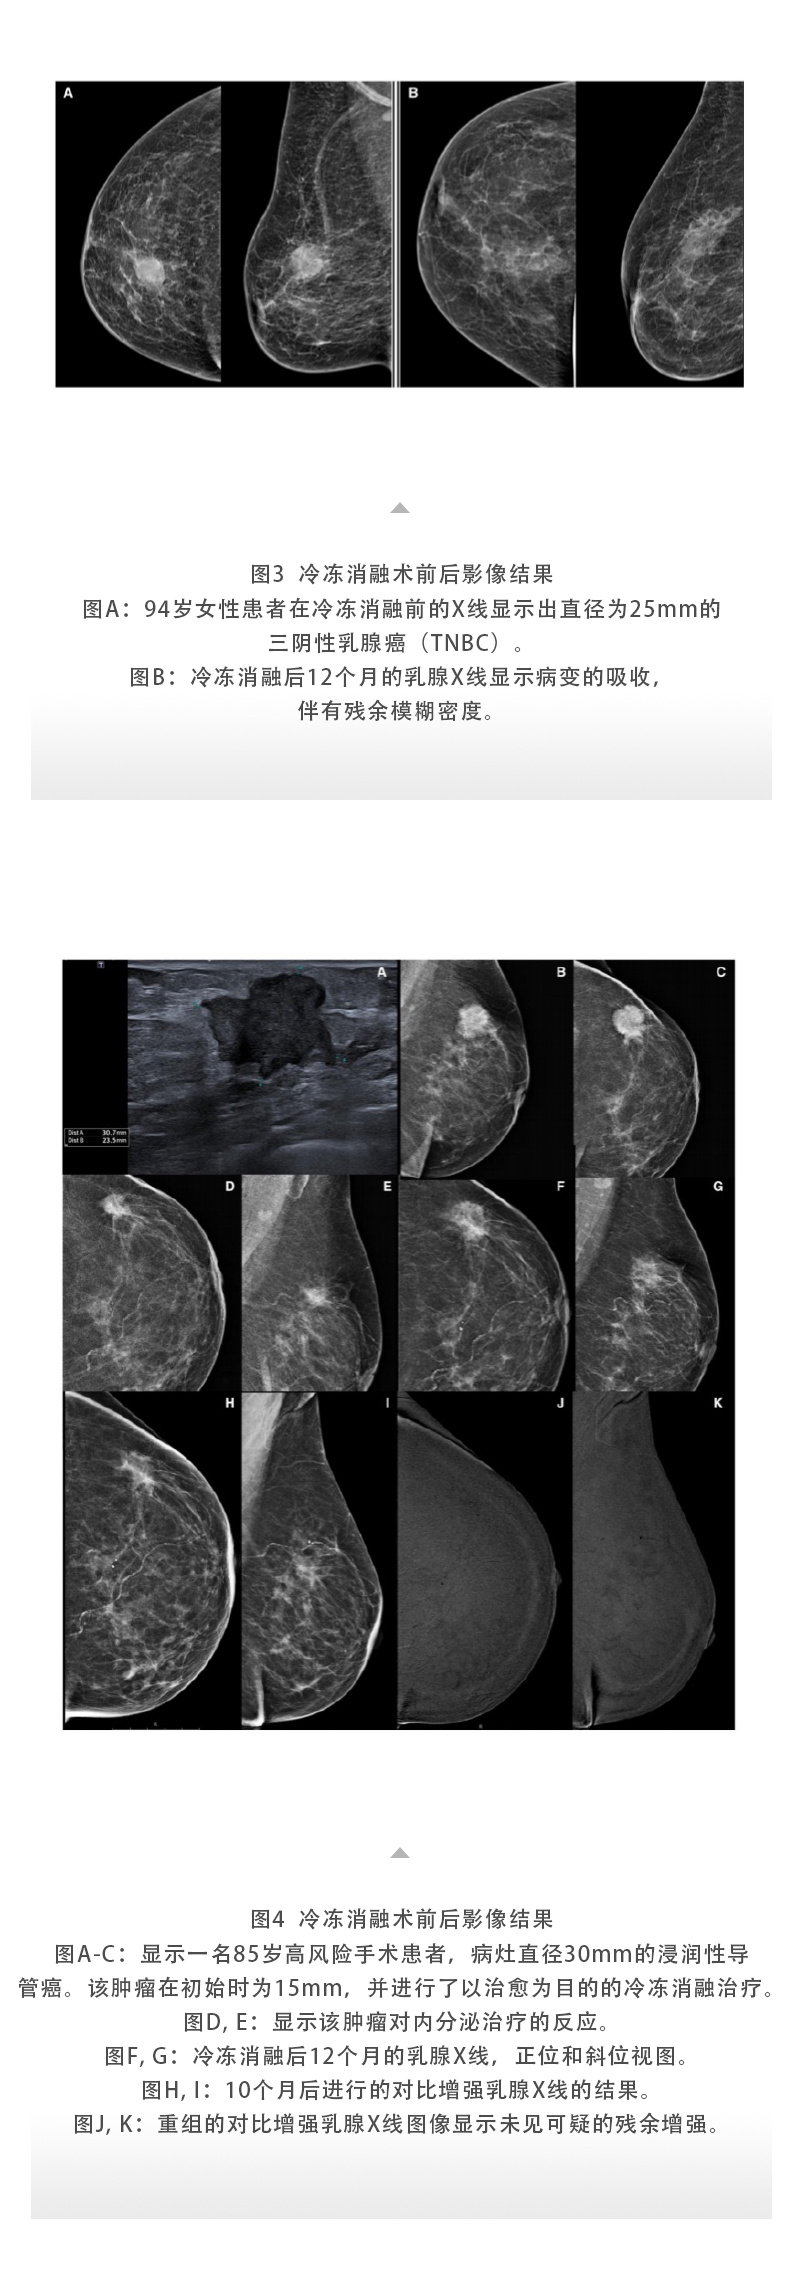

【HYGEA·科研資訊】乳腺癌冷凍消融